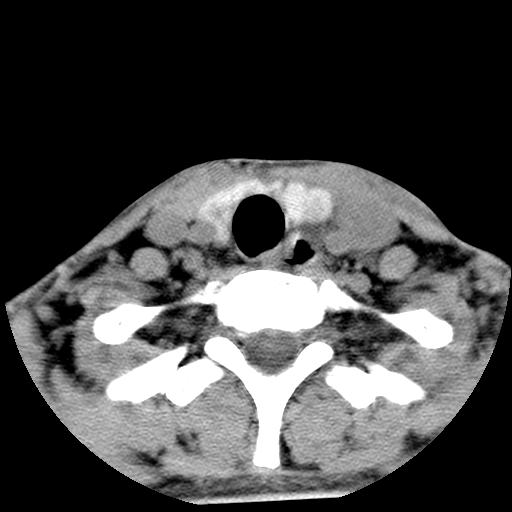

标题: CT15118:f-27y,左颈部肿一个月,无发热、无压痛 [打印本页]

标题: CT15118:f-27y,左颈部肿一个月,无发热、无压痛

1、甲状腺左叶病变:腺瘤?结节性增生?其他?

2、上极周围间隙病变。

3、2者关系?

左侧甲状腺肿大,密度不均.同侧甲状软骨似有破坏(建议传骨窗).左侧颈静脉增粗,各组织之间分界不清,有多个肿大淋巴结.甲状腺肿并感染?临床症状不符.淋巴结核?请结合其他检查.